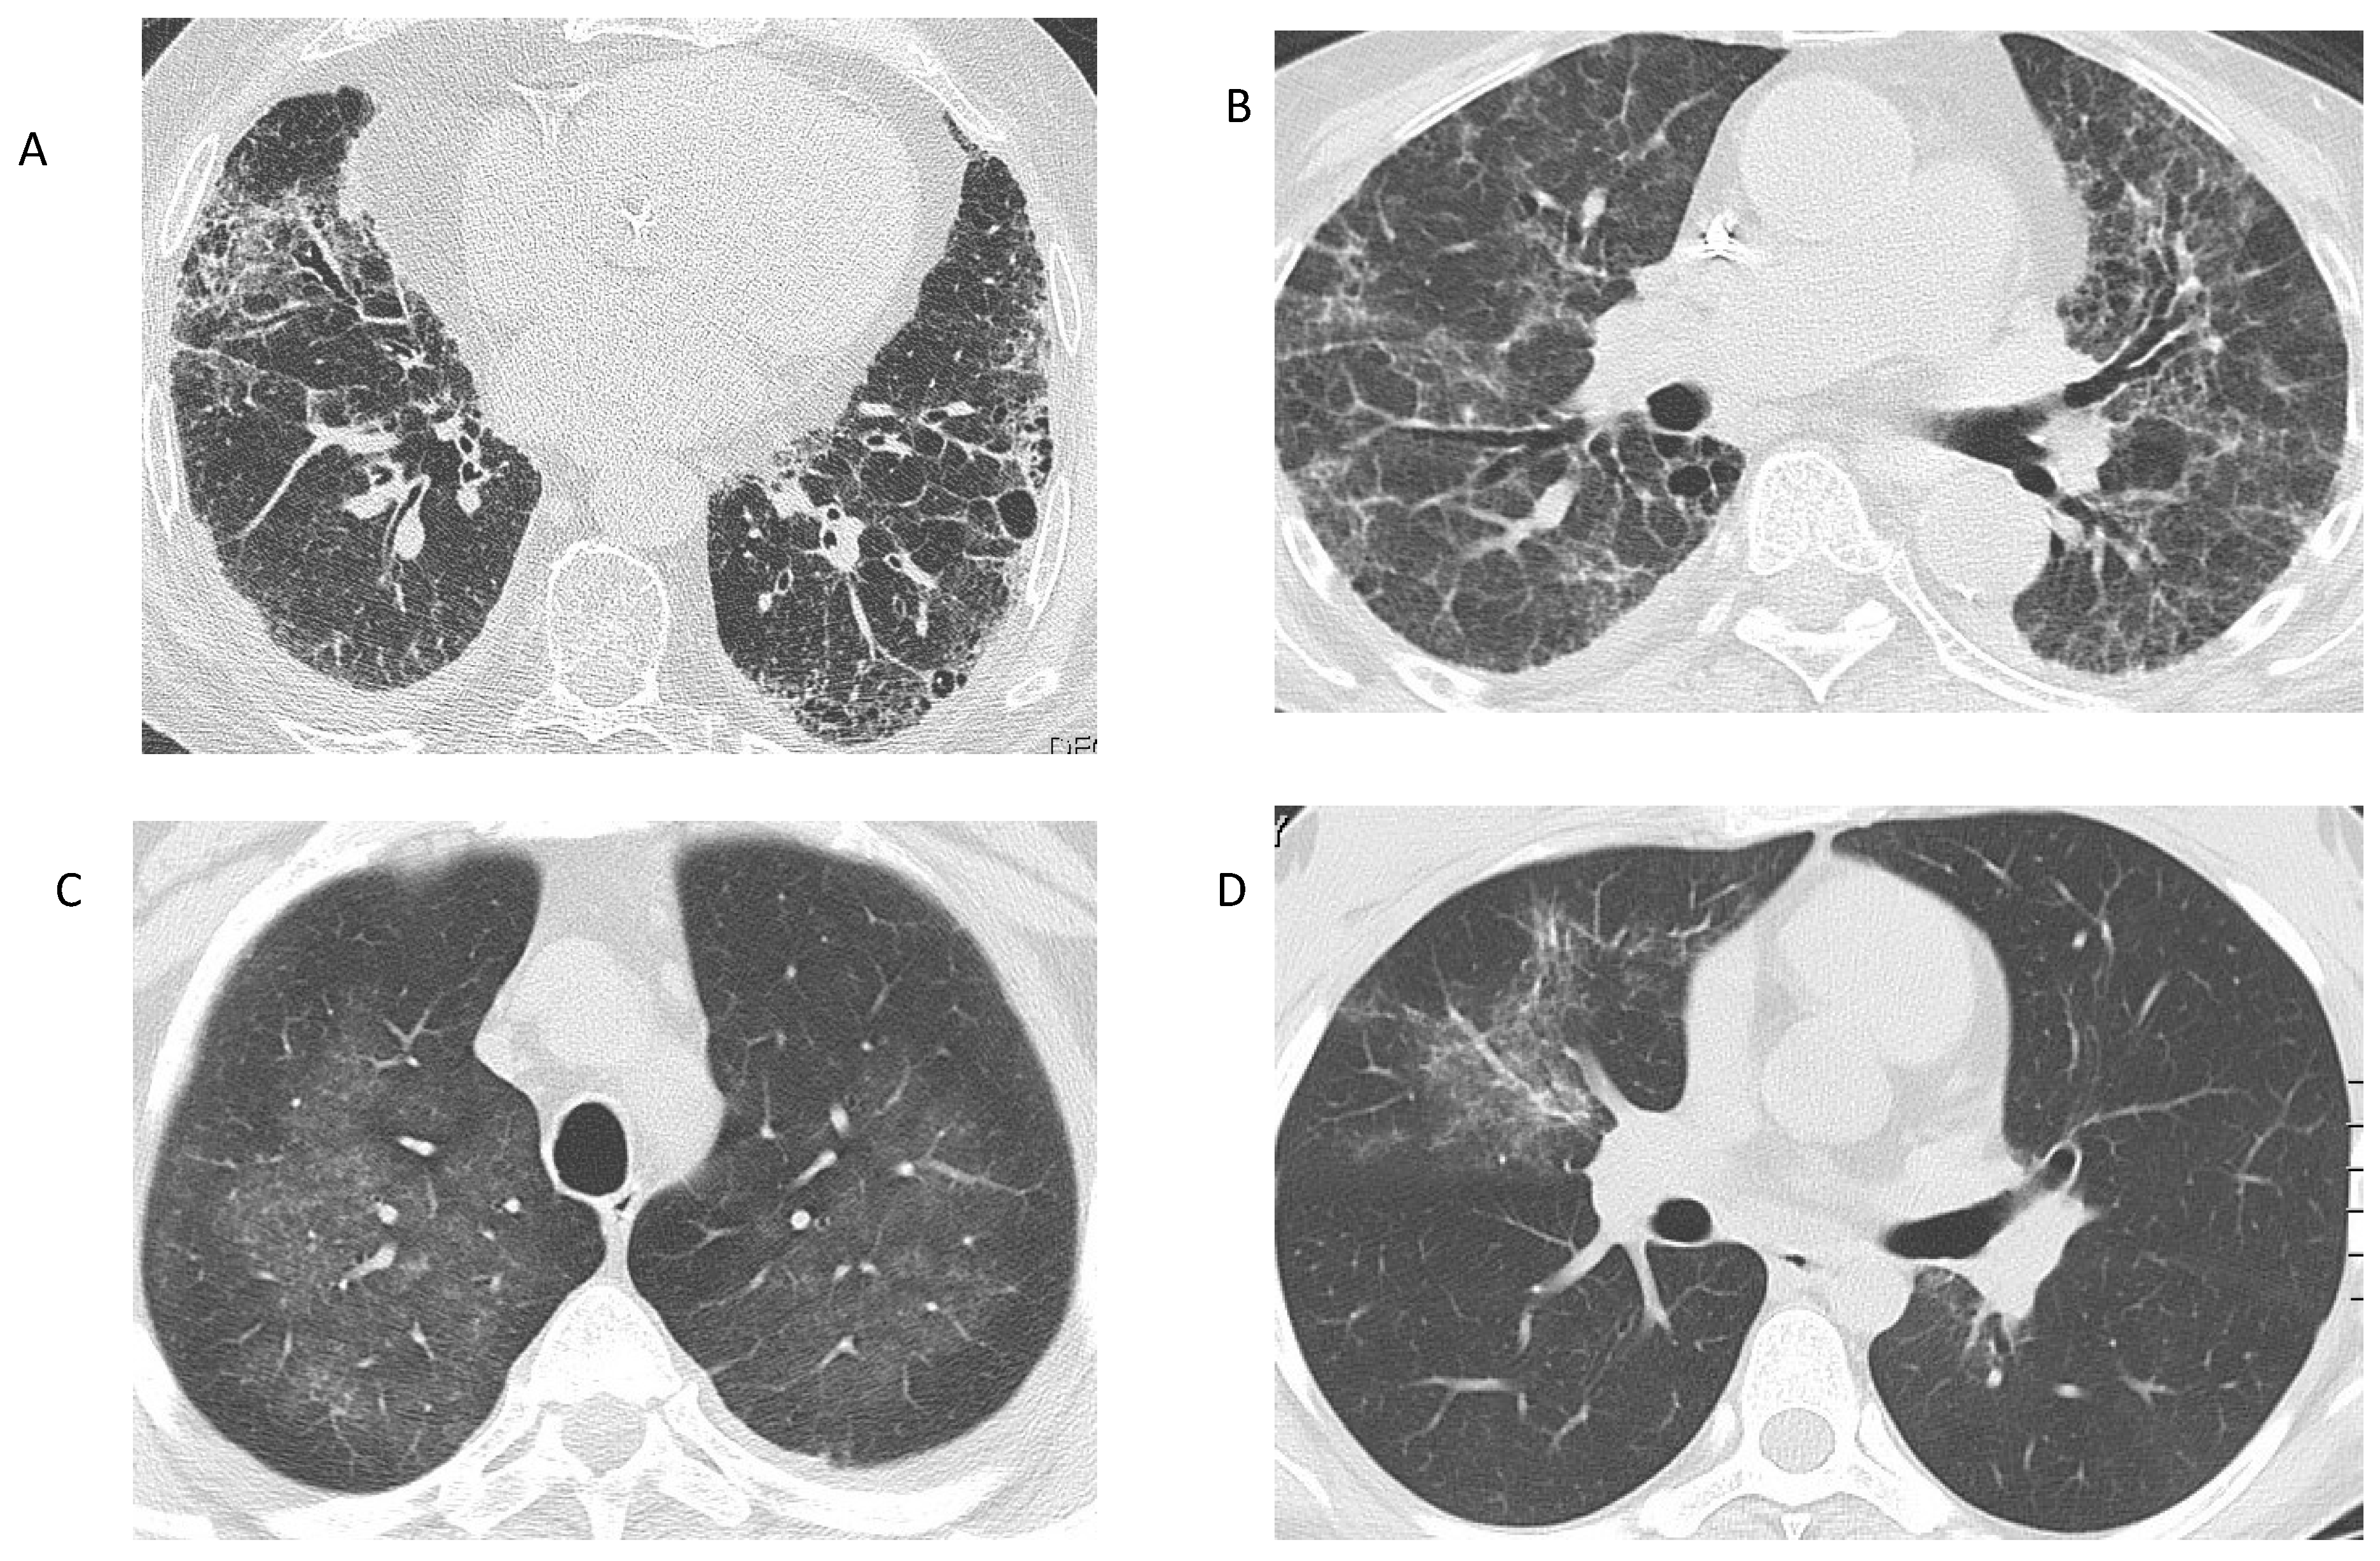

Figure 1.

Radiographic findings in AAV. (A) Interstitial lung disease in a patient with MPA. Reticular opacities at the basal and peripheral lung segments, corresponding to a UIP pattern. (B) Interstitial lung disease in a patient with MPA, who presented with acute renal failure. Reticular changes and ground-glass opacities, suggestive of an NSIP pattern. (C) Ground-glass opacities in a patient with GPA: Bronchoalveolar lavage revealed alveolar hemorrhage. (D) Ground-glass opacity in the right upper lobe of a patient with EGPA, representing eosinophilic infiltration of the lung. (Images from the personal archive of Prof. Steiropoulos).